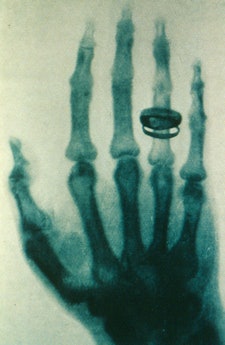

One of Roentgen's early images.

One night, to explain his experiment to his wife, he made an x-ray image of her hand. The bones and the ring appeared, but the flesh was not seen. His wife was frightened, but Roentgen was convinced that he understood the presence of the invisible x-rays and their ability to make images of dense objects and living human bones.